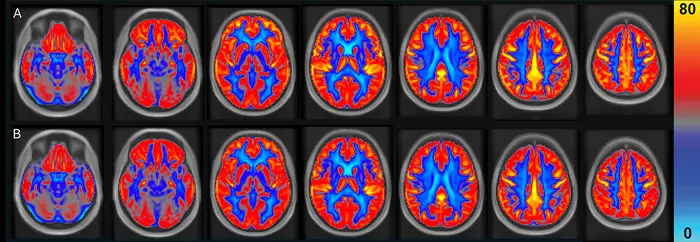

Arterial spin labeling magnetic resonance imaging (MRI) was used to investigate the effects of daily peanut consumption on brain health.

Figure 1. Mean cerebral blood flow (CBF) maps following the (A) peanut intervention and (B) control periods in adults (n = 31). CBF displayed in mL/100 g/min (scale shown by color bar).

The NUTRIM study of 31 healthy older adults ranging in age from 60-75 observed that consuming 60 grams (approximately two servings) of peanuts daily for 16 weeks increased global cerebral blood flow (CBF) by 3.6% and verbal memory by 5.8%. In addition to the brain improvements, systolic blood pressure and pulse pressure decreased by 5 mmHg and 4 mmHg, respectively.

“CBF is an important physiological marker of brain vascular function and refers to the amount of blood that flows through the brain, delivering oxygen and nutrients that are essential for maintaining brain health,” says Dr. Peter Joris, the study’s author and an associate professor in the Department of Nutrition and Movement Sciences, NUTRIM, Maastricht University Medical Center. “We found that longer-term consumption of unsalted, skin-roasted peanuts improved global CBF, which suggests an overall enhancement in brain vascular function.”

The peanut intervention also resulted in increased blood flow in the frontal and temporal lobes of the brain, both of which are important for memory and other cognitive functions.